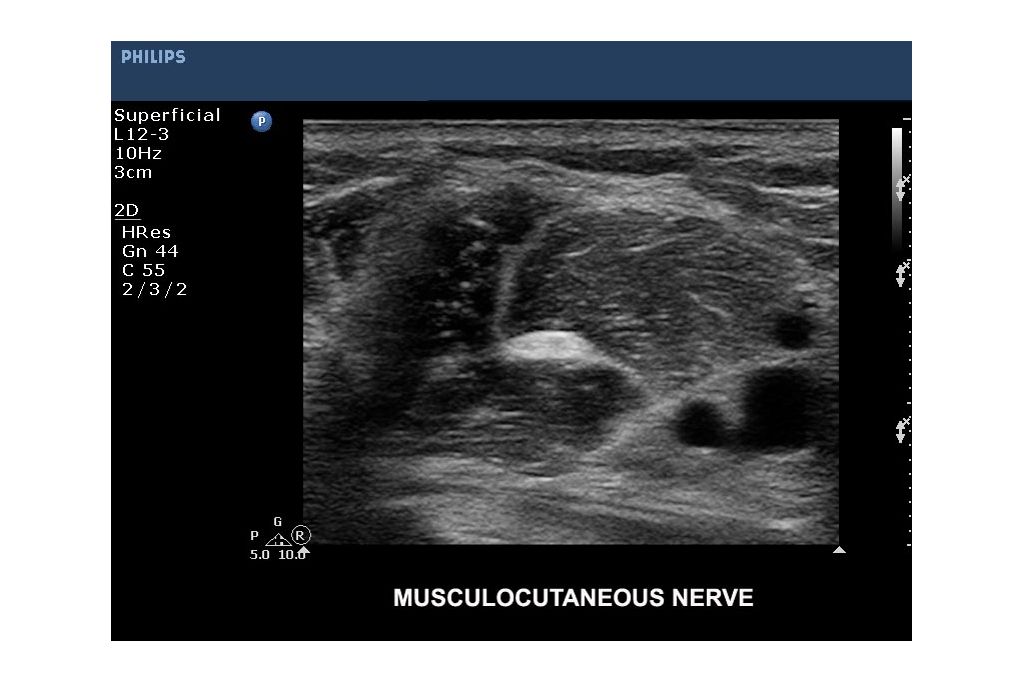

CX 50 - Circular Edition - Refurbished Ultrasound Machine and System | Philips Healthcare